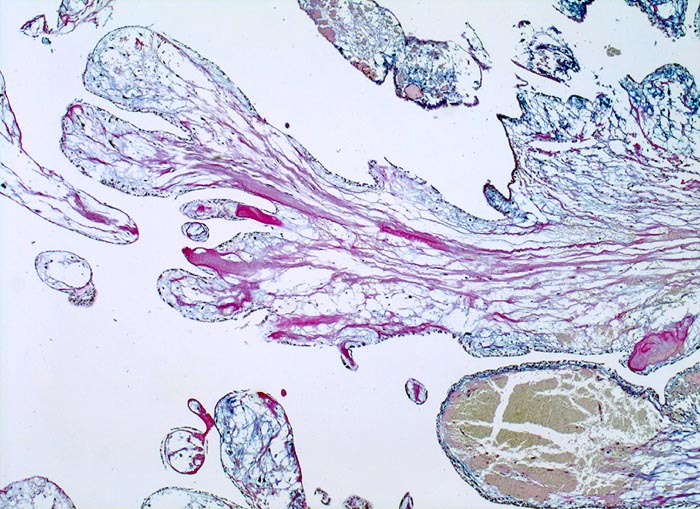

AP/ Vorhofmyxom

Vorhofmyxom

Herz Vorhof